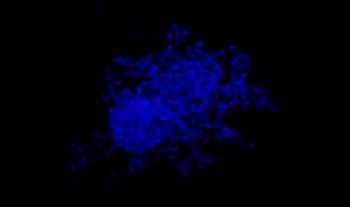

Making the spheroids transparent and imaging them with an FV3000 confocal laser scanning microscope enabled us to image the co-cultured cancer spheroids at depth. Staurosporine treatment increased the number of dead cells in a dose-dependent manner (Fig. 2*1). Three-dimensional analysis is required to determine which cells are dead and how many dead cells there are in a three-dimensional mass.

Figure 2. Drug response in co-culture spheroids

Figure 2. Drug response in co-culture spheroids*1